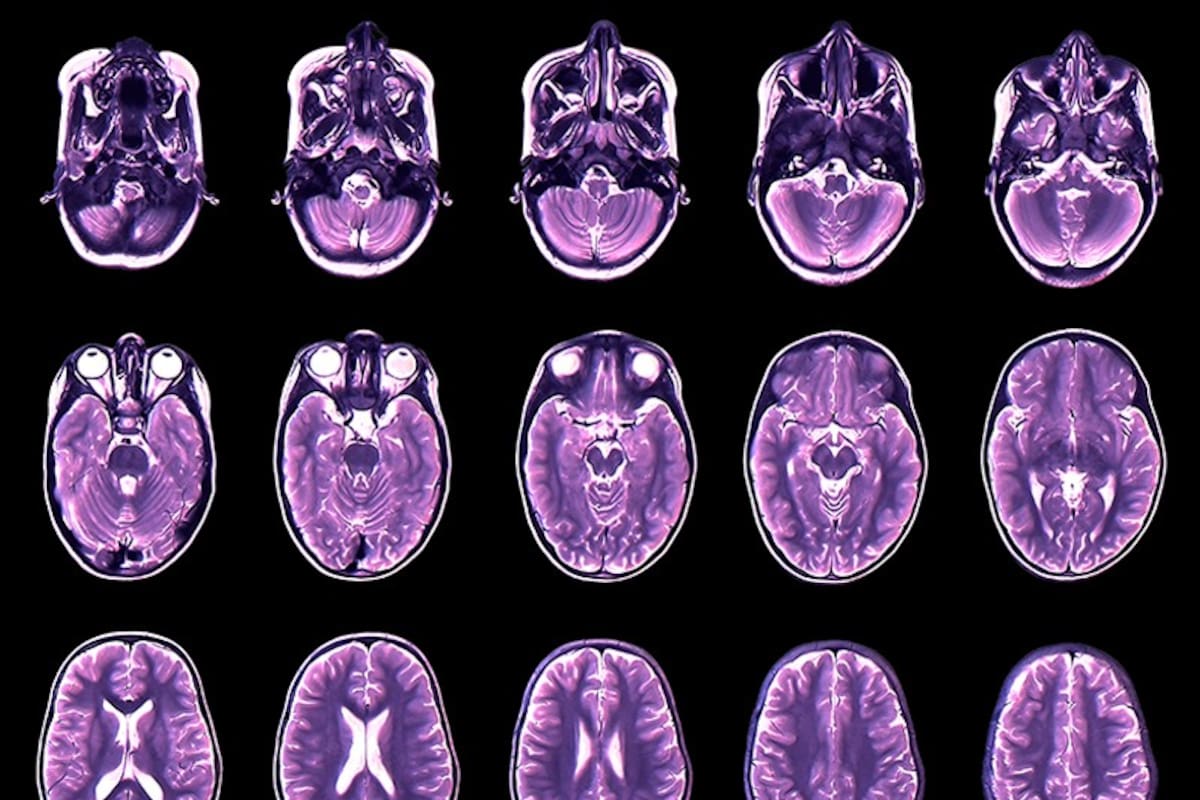

El estudio, realizado por investigadores de la Universidad de Pensilvania (Estados Unidos) y publicado en la revista Nature, confeccionó un mapa de referencia para el crecimiento del cerebro mediante el análisis de 123.984 resonancias magnéticas procedentes de todo el mundo.